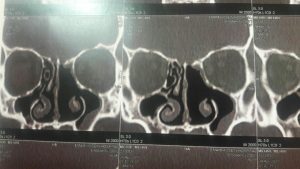

2. سی تی اسکن

تشخیص به وسیله این روش تصویربرداری دقیق تر از سایر روشها می باشد زیرا میزان درگیری استخوان از این طریق نشان می دهد. همچنین برای تشخیص تومور در اطراف مغز از این روش استفاده می شود.

این عکس ها متعلق به خانمی ۵۲ ساله با سابقه گرفتگی بینی از چند سال قبل و نیز سابقه جراحی پولیپ در ۱۰ سال گذشته می باشد در بررسی بالینی نکته دیگری جز توده ای به ظاهر پولیپ مانند در بینی نبود. محل کلی تومور با خط مشکی مشخص شده است

فلش نارنجی محل منشا تومور درنازکترین استخوان حدفاصل بینی ومغز را نشان می دهد.

که در تصویر برداری با سی تی اسکن بینی و سینوس نمای موجود شک به این نوع پاپیلوم را برمی انگیخت که طی عمل جراحی اندوسکوپیک و کمک مداوم سر جراحی از همکاران پاتولوژیست وجود این توده ثابت گردیید. و متاسفانه محل پیدایش و منشا اولیه آن در قاعده جمجمه و در محل نازک ترین قسمت استخوان بین بینی و سینوس ها و مغز به طور عملی محرز گردید و این نایحه به طور کامل با کمک ابزارهای خاص تراشیده شده و عمل با اطمینان از برداشت کامل بدون آسیب و صدمه به عناصر حیاتی نظیر مز خاتمه پیدا کرد.